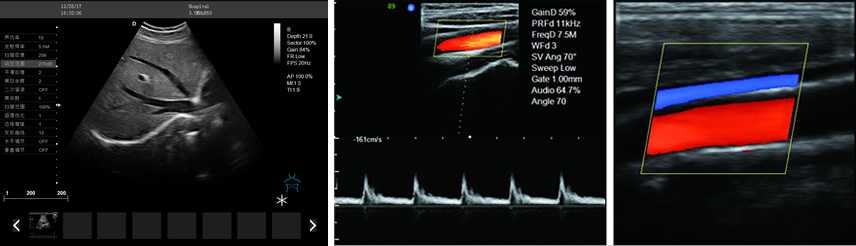

產(chǎn)品性能:高集成數(shù)字式彩色多普勒技術(shù),寬頻探頭,強(qiáng)勁的組合式模塊化軟件設(shè)計,全數(shù)字式大容量圖像存貯和文件歸檔管理,適用范圍:用于人體超聲診斷檢查。

廣泛的臨床應(yīng)用

優(yōu)質(zhì)成像 便捷操作